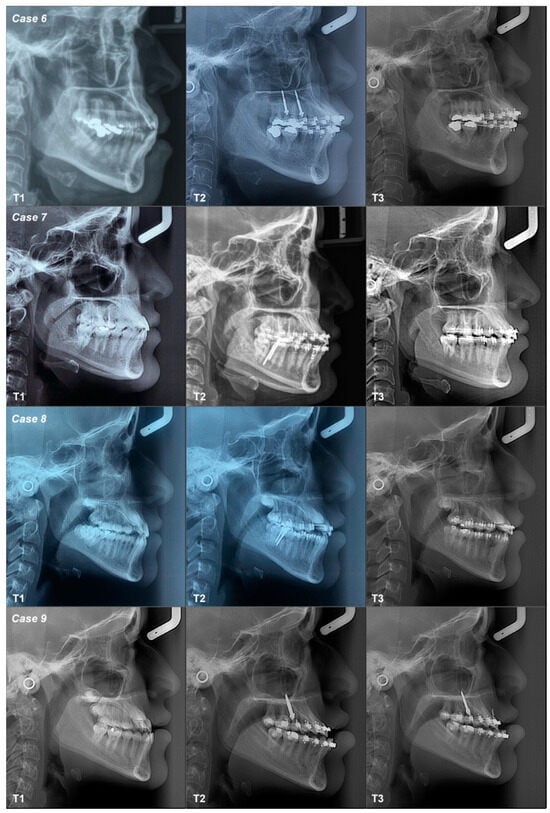

3.2.6. Case 6

3.2.7. Case 7

3.2.8. Case 8

3.2.9. Case 9